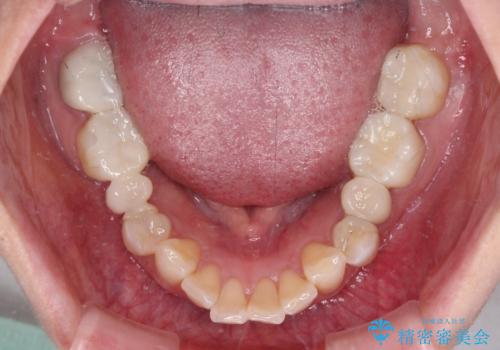

- クラウンから金属の土台が見えてきてしまったとのことで、作り替えを希望して来院された患者様です。

前歯や金属が露出している歯、痛みを感じる歯を中心に、オールセラミッククラウンにて補綴治療することとしました。